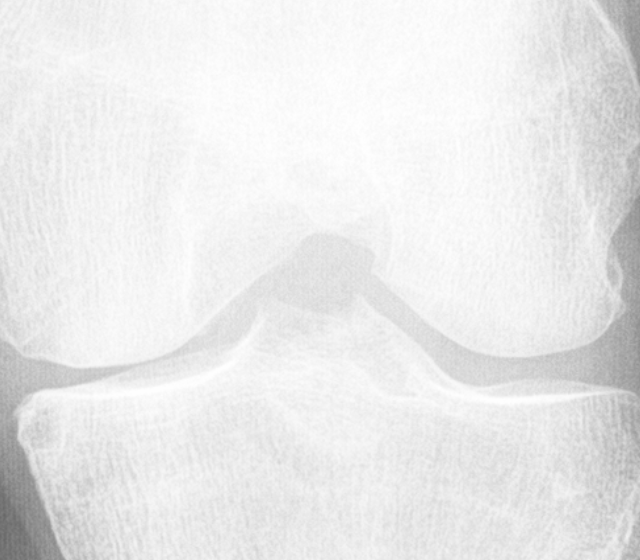

Knee OA develops gradually over years and progresses in stages. In general, the severity of knee OA is divided into five stages. The first stage (stage 0) corresponds to normal healthy knee and the final stage (stage 4) corresponds to the most severe condition (see Figure 2). The most commonly used systems for grading knee OA are the International Knee Documentation Committee (IKDC) system, the Ahlback system, and the Kellgren & Lawrence (KL) grading system. The other widely used non-radiographic knee OA assessment system is WOMAC666Western Ontario and McMaster Universities Osteoarthritis Index, which measures pain, stiffness, and functional limitation. The public datasets, the OAI and the MOST used in this work, are provided with the KL grades and they are used as the ground truth to classify the knee OA X-ray images.

Refer to caption

Figure 2: The Kellgren and Lawrence grading system to assess the severity of knee OA.

The KL grading scale was approved by the World Health Organisation as the reference standard for cross-sectional and longitudinal epidemiologic studies [7, 22, 24, 25]. The KL grading system is still considered the gold standard for initial assessment of knee osteoarthritis severity in radiographs [1, 5, 6, 7]. Figure 2 shows the KL grading system. The KL grading system categorizes knee OA severity into five grades (grade 0 to 4). The KL grading scheme for quantifying knee OA severity from X-ray images is defined as follows [1, 5]:

• Grade 0 : absence of radiographic features (cartilage loss or osteophytes) of OA.

• Grade 1 : doubtful joint space narrowing (JSN), osteophytes sprouting, bone marrow oedema (BME), and sub-chondral cyst.

• Grade 2 : visible osteophytes formation and reduction in joint space width on the antero-posterior weight-bearing radiograph with BME and sub-chondral cyst.

• Grade 3 : multiple osteophytes, definite JSN, sclerosis, possible bone deformity.

• Grade 4 : large osteophytes, marked JSN, severe sclerosis, and definite bone deformity.